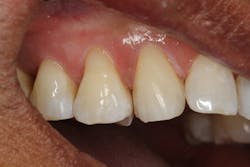

A 45-year-old male presented for three class V fillings. Teeth nos. 4 and 5 had cervical abrasions (or erosion), and no. 6 had a defective existing composite fillingThe teeth to be restored in this case had excellent gingival health, and the patient was in good health. The patient was anesthetized with one carpule (1.7 ml) of lidocaine with 1:100,000 epinephrine.